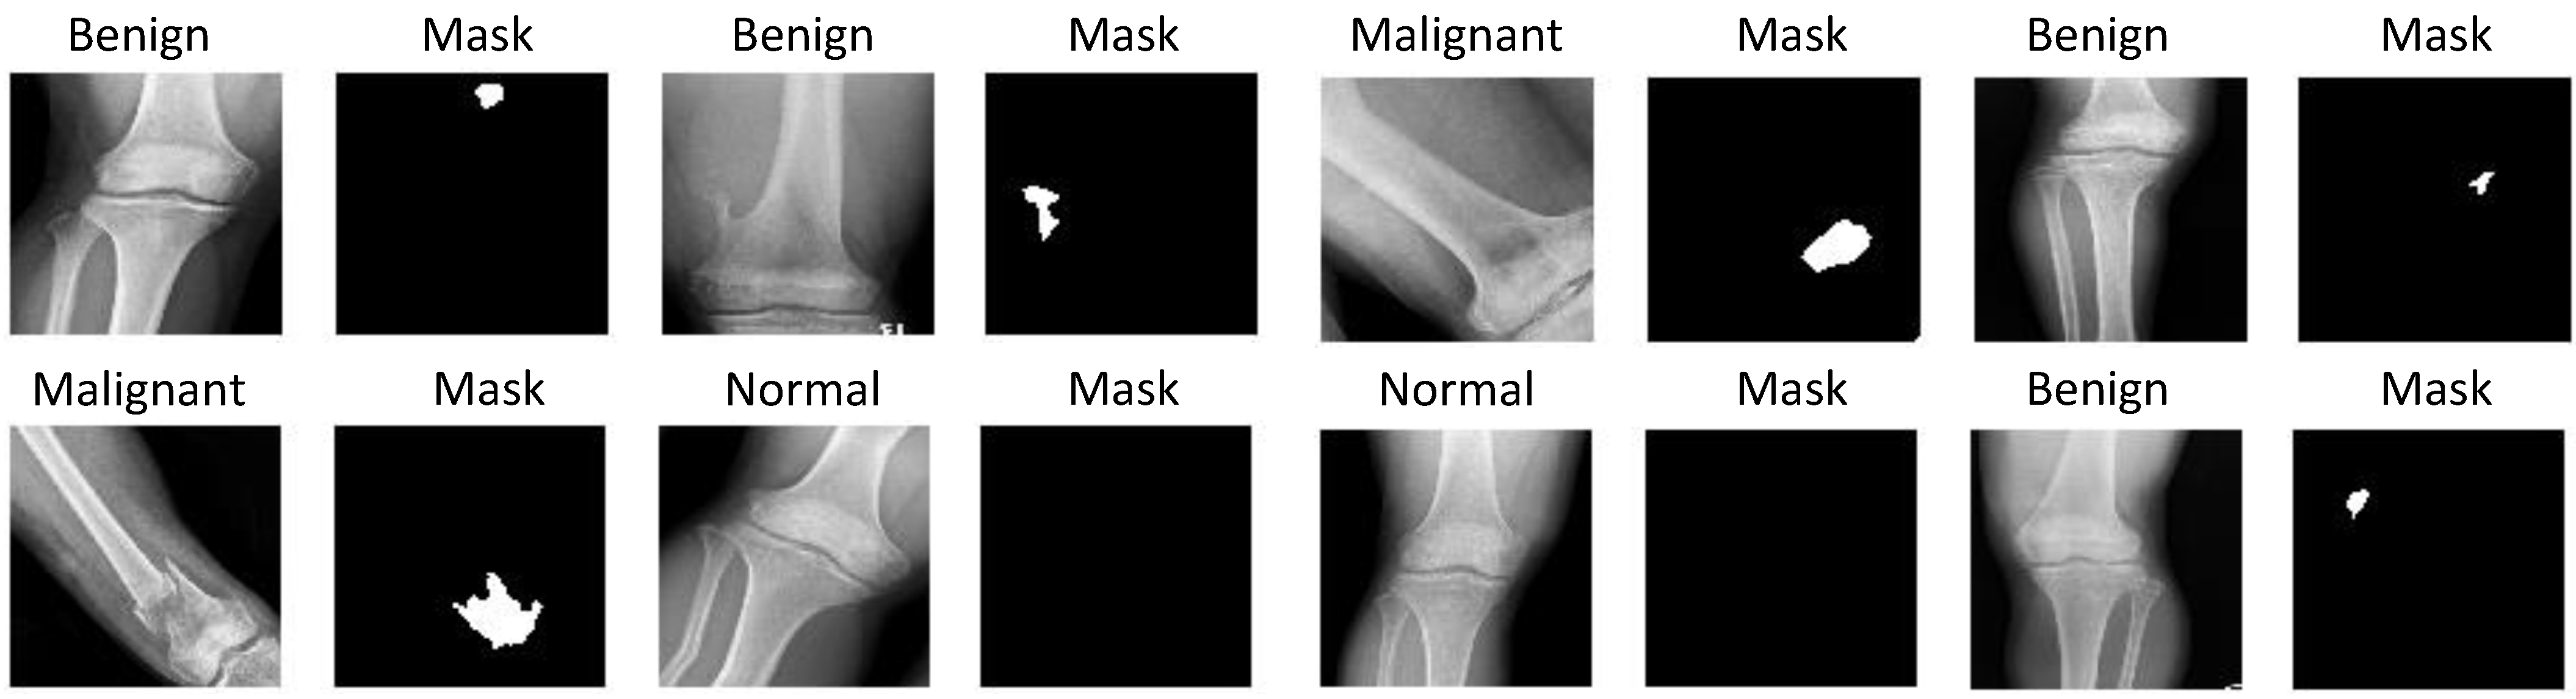

2.2.2. Global and Patch-Based Models

3.1. Experiments on Tumor Segmentation